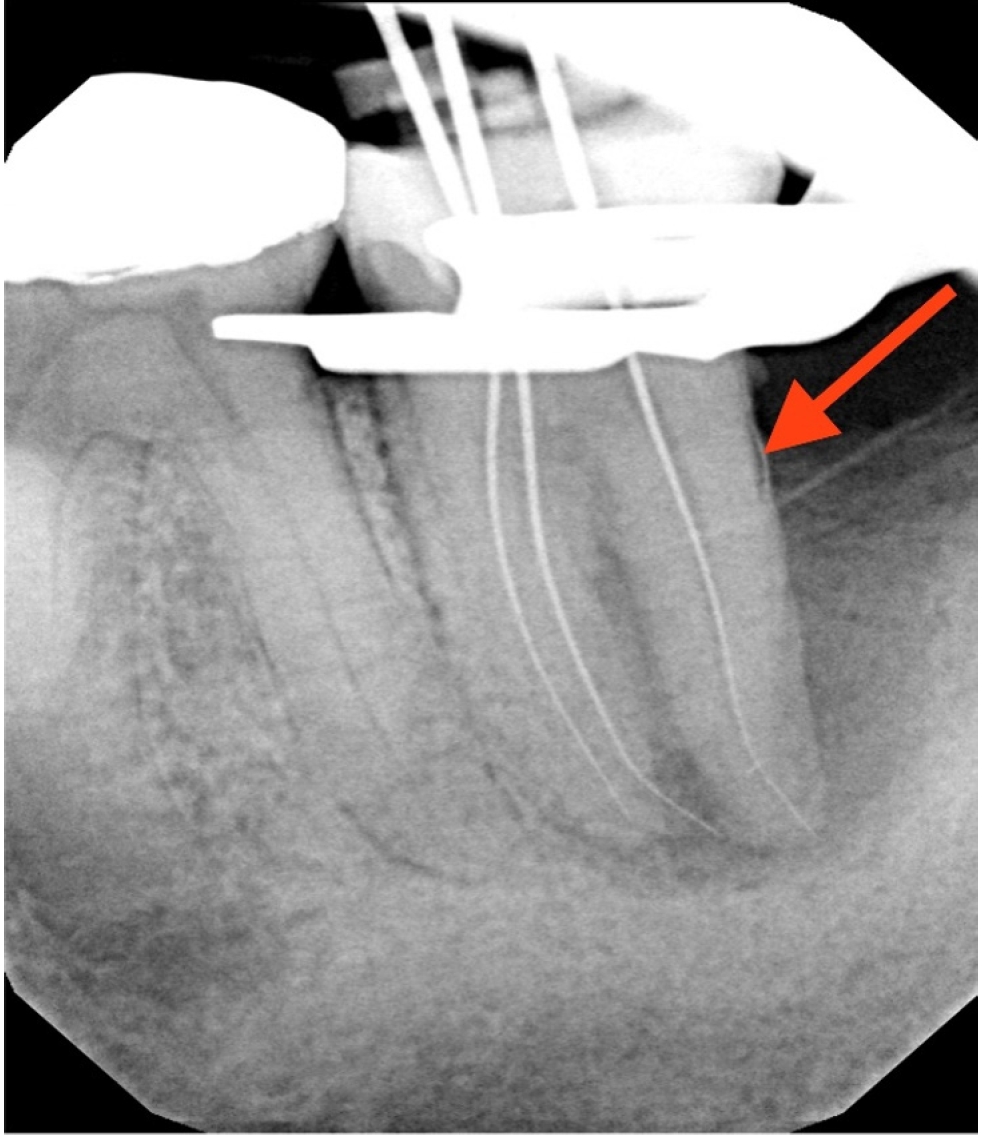

Working lengths were determined using an electronic apex locator (RootZX; J Morita, Kyoto, Japan) and confirmed with a periapical radiograph, which also showed a radiopaque fragment consistent with a cemental tear (Figure 2). The chamber was flooded with 5% sodium hypochlorite, and the canals were instrumented using size 8, 10, 15, and 20 K files, followed by a 25/.07 Primary Wave One Gold (Dentsply Sirona, Charlotte, NC, USA) reciprocating file. Irrigation was performed with 12 mL of 5% sodium hypochlorite with ultrasonic activation for 30 seconds per canal. Calcium hydroxide was placed as an intracanal medicament with a lentulo spiral, and the tooth was temporized with a sterile sponge and Cavit (3M ESPE, St. Paul, MN, USA). The patient was informed to return in 2 weeks for completion of the root canal.

Figure 2.

Working length radiograph showing radiopaque fragment consistent with a cemental tear along distal root (red arrow).